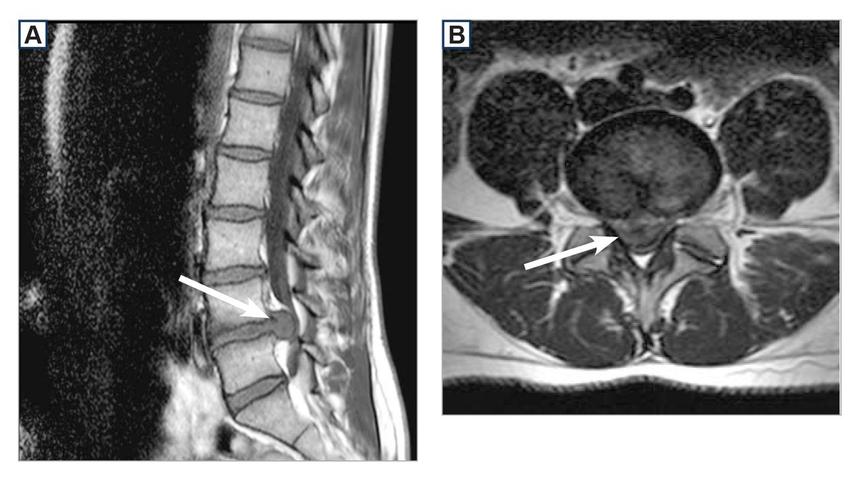

Вот так выглядит грыжа на снимке